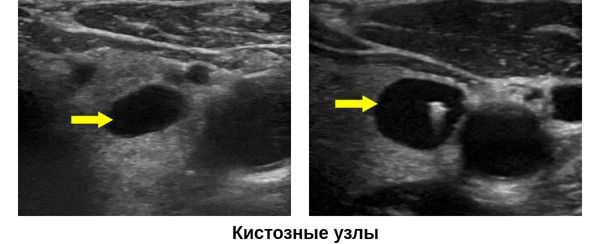

5. УЗИ при коллоидной кисте щитовидной железы:

• Серошкальное УЗИ:

о Тонкостенное образование с четкими контурами

о Анэхогенное, трансмиссия повышена

о Коллоидные кристаллы могут быть взвешены в жидкости; артефакт по типу хвоста кометы